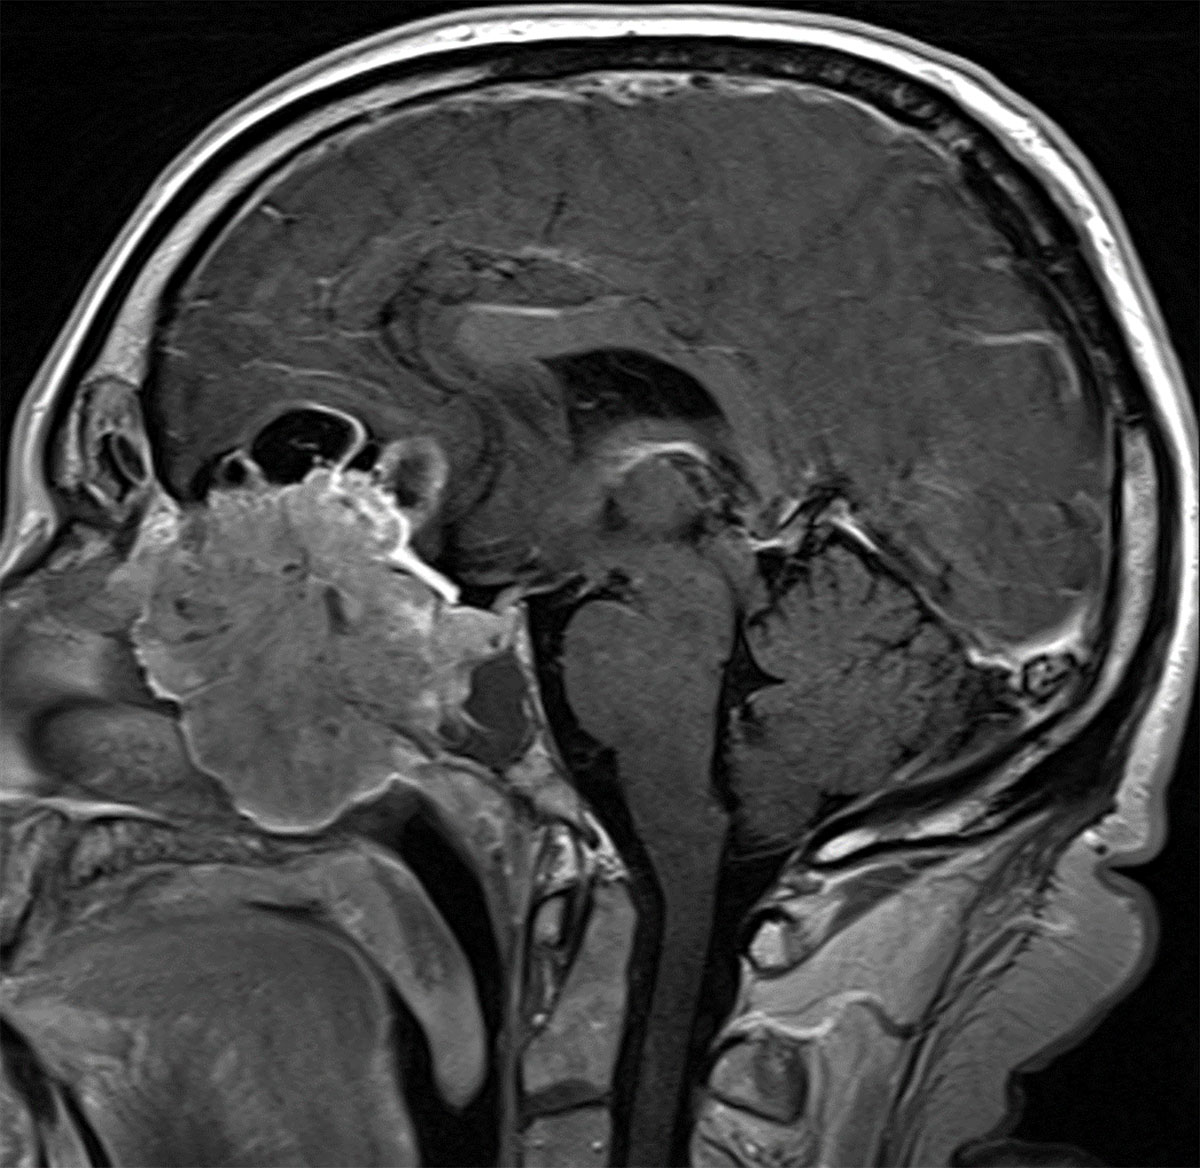

Figure 3

Olfactory neuroblastoma. This malignant neuroectodermal tumour arises from the olfactory epithelium in the superior nasal cavity and often extends intracranially across the lamina cribrosa, as is depicted on this sagittal post-contrast T1-weighted MR image.